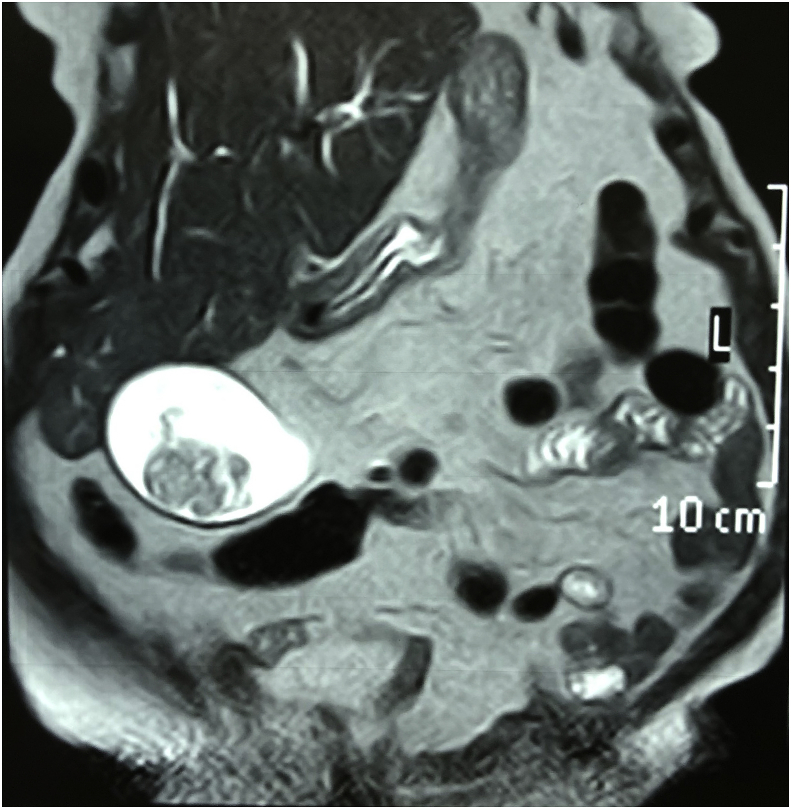

Diagnostic Assessment: Investigations showed elevated white blood cell count 14000 cmm, bilirubin level was 2.3 mg/dl and elevated alkaline phosphatase 842 IU/L. Ultrasound and magnetic resonance cholangiopancreatography showed evidence of multiple gall stones with a large irregular polyp in the region of the fundus of the gall bladder, and dilated common bile duct with evidence of multiple stones in the lumen of common bile duct. Figs. 1 and 2